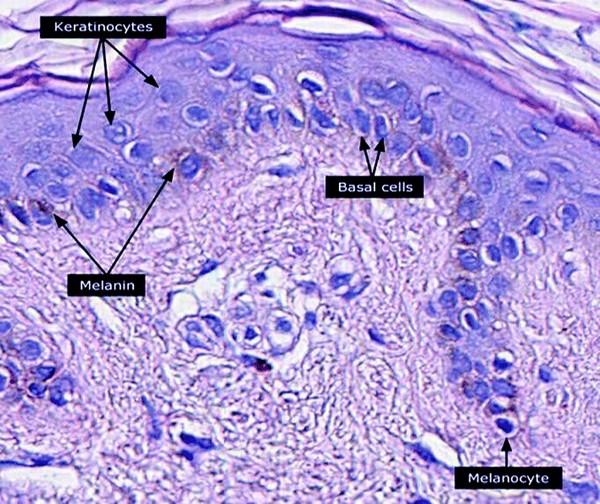

Fig. 5. Keratinocytes, basal cells and melanocytes

- Account for about 80% of the cells of the epidermis. Keratinocytes are cornified epithelial cells that serve as a barrier to the environment. In wound healing, coverage of keratinocytes represent the final step of wound repair (re-epithelialization).

- Keratinocytes have high quantities of protein in their cytoplasm, which is mainly composed of keratin and keratohyalin (or filaggrin).

- Function: keratinocytes give the epidermis structural and tensile strength

- Cell differentiation: keratinocytes originate in the basal layer and migrate to the stratum corneum over 45-70 days (the actual duration of this process may vary, being shorter in patients with psoriasis or longer in the elderly). In full thickness wounds, keratinocytes migrate only from free wound edges. In partial thickness wounds, keratinocytes migrate from free wound wedges as well as adnexal (appendage) structures.

- The second most common cell type in the epidermis, accounting for about 19% of the epidermal cell population.

- Location: basal layer

- Function: melanocytes play major roles in skin pigmentation (they produce a pigment called melanin), skin homeostasis and wound healing. Melanocytes are responsible for contributing to the color of our skin, along with carotene and hemoglobin. Melanocytes may also be considered as “cutaneous neurons”, due to their embryologic origin in the neural crest cells and other structural similarities such as cell bodies, axons, dendrites and synapses with neurotransmitters.